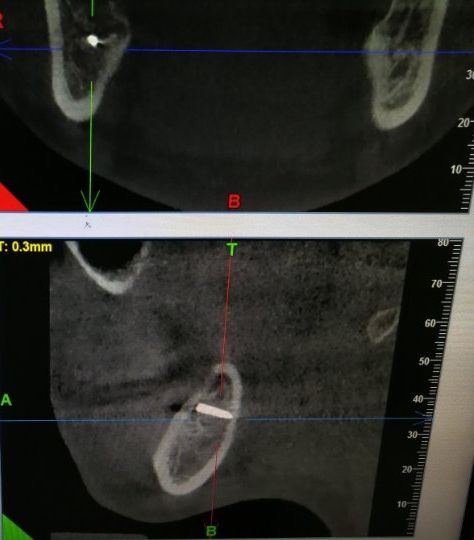

李女士口腔内的金属物。这一检查,把她吓了一跳。据其在松岗人民医院口腔科拍摄的x光片显示:她之前拔掉的智齿牙窝里,残留了两节金属物,并且已经没入很深,快要接近下颌神经管了。如果再深一点,可能会导致其面部神经损坏。“我听到,差点吓哭了。”李女士说。自己当时因为想省点钱,就去了小诊所,没想到竟然发生了这样的事情。好在后来去医院还算及时,医护人员确定位置和异物大小等情况后,利用超声骨刀把李女士牙窝中的异物取了出来。后经十余天的输液治疗,李女士的情况已经基本恢复。

取出的金属物长约1公分。那么,嵌入李女士牙窝中的金属物质到底是什么呢?松岗人民医院口腔科医生石健介绍,医院接诊后,为患者拍摄了X光片。从X光片可以看到,李女士拔牙创口有一个密度很高的金属影,长度约1公分。经联系李女士拔牙的诊所医生了解到,这个异物可能是拔牙用具“压挺”的尖端碎片。“牙挺是靠撬力来拔出牙齿的,医生如果用力不当,偶尔会将牙挺尖端折断,遗留在患者的牙窝内。”石健医生说。据介绍,因异物嵌入很深,快要接近神经管,取出时风险较大。后经商议,决定使用超声骨刀帮患者将异物取出。李女士表介绍,事发后,当时为其拔牙的小诊所对此进行了道歉和赔偿。